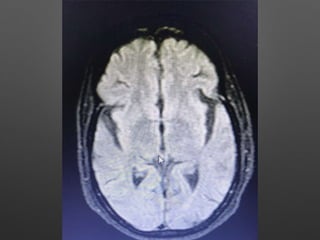

Investigations

• HB- 14.1gm% - 12.2

• WBC- 15990cells/cumm - 10770, -P 83%, L-9%,M-7%

• Platelets - 3.3lakhs - 2.8

• ESR- 63mm/hr

• RBS - 267 mg/dl

• CUE - N

• RFT - N

• LFT - N

• S.Na - 137, k+ - 3.9, Mg- 2.1, Ca- 9.1, Ph- 3.5, Ammonia- 0.29

• ECG - N

• 2DEcho- N

• U/S - Abd- Gr I Fatty liver changes

Investigations • HB- 14.1gm%- 12.2 • WBC- 15990cells/cumm - 10770, -P 83%, L-9%,M-7% • Platelets - 3.3lakhs - 2.8 • ESR- 63mm/hr • RBS - 267 mg/dl • CUE - N • RFT - N • LFT - N • S.Na - 137, k+ - 3.9, Mg- 2.1, Ca- 9.1, Ph- 3.5, Ammonia- 0.29

• 9.

• ECG -N • 2DEcho- N • U/S - Abd- Gr I Fatty liver changes